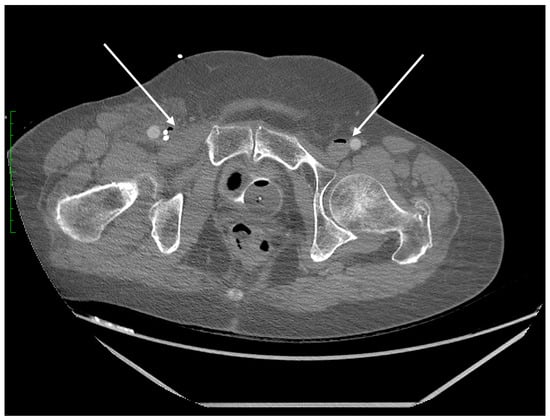

Figure 3. Axial plane of the abdominopelvic CT scan after intravenous contrast administration (delayed phase) at the pelvic level. Gas bubbles are recognizable in the lumen of both femoral veins (arrows).

Due to the high solubility of carbon dioxide, the diagnostic imaging performed in a short interval after the SCA exceptionally illustrates the mechanism of gas bubble transmission into the vasculature of both vena cavae. We were able to visualize the presence of CO2 gas in the CT scan of the head in Figure 5 and in the distal section of the CT scan of the abdomen and pelvis which includes a section of the lower extremities in Figure 3. The explanation for such extensive gas transfer and its presence in the internal jugular vein, craniofacial tissues, sigmoid sinuses of the superior vena cava (Figure 5) and in the lumen of the femoral veins (Figure 3) may be explained by the CPR performed, and the possibility of very high pressures of the gas used, which may have been facilitated by the hypovolemic position and status of the patient.